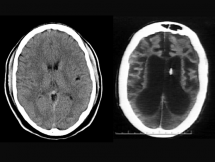

Understanding human anatomy, and how to diagnose and treat illnesses, has changed dramatically from ancient to modern times. This collection features people whose medical breakthroughs helped to save millions of lives.